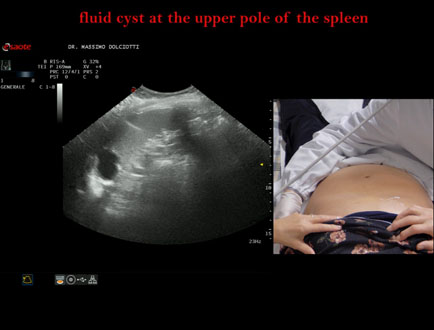

Data inserimento: 12/11/2025

Ecografia del: 05/11/2025

Strumento: Esaote MyLab Eight

Sonda: Convex Multifrequenza 1-8 MHz

Età Paziente: F 52 anni

Motivazione dell'esame: follow up per cisti splenica.

Commento all'esame: le immagini ed il video documentano al polo superiore della milza, formazione anecogena, con pareti superiori calcifiche, da ricondurre a cisti splenica.

Conclusioni: cisti liquida al polo superiore della milza (fluid cyst at the upper pole of the spleen).

Presentazione: Dr. Massimo Dolciotti - Ancona

Elaborazione digitale: Andrea Dini - Ancona